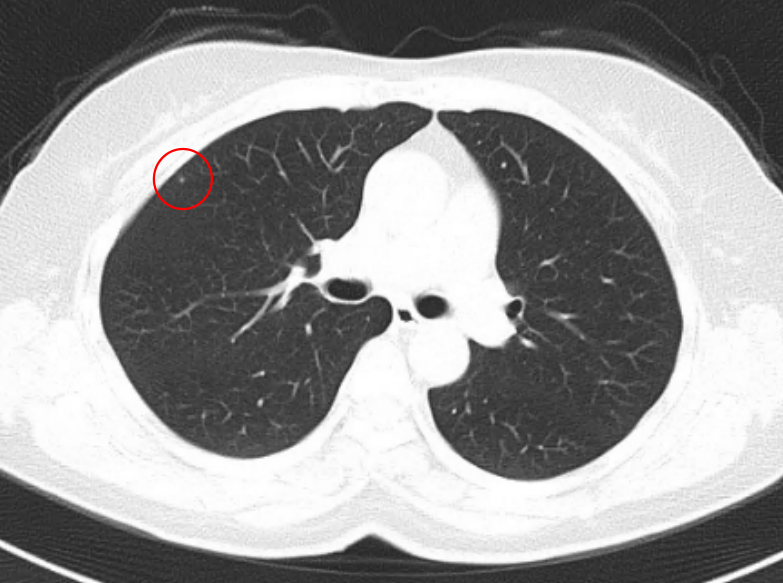

徐燕医生解释,如上图所示,肺上长了一个特别小的结节,它距离支气管非常远,也并不临近胸膜,像这样的肺小结节,不会导致咳嗽、咳痰以及后背疼痛的这些症状,上述症状也许是因为其他的原因导致的,还需要再寻找病因。除非是有些肺结节相对来讲比较大,恶性程度高,可能在早期发生了转移,导致了相应的症状。但是大部分的肺内小结节和微小结节不太可能会出现早期转移。

如图所示,红圈处就是一个肿块,这个病灶已经超过5cm,相对来讲它就不太可能是早期的肿瘤了,经过系统的评估,这个肿瘤最终确定是晚期肺癌。所以,现在做低剂量螺旋CT肺癌筛查很重要的意义就是发现早期的肺癌,而避免肿瘤到了很晚期出现了症状再被发现。如果真是是早期肺癌,患者有机会行手术治疗,预后会比较好;如果诊断时分期比较晚,患者的治疗和愈后相对来讲会比较差。